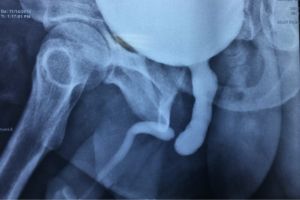

در این مرکز ابزارهای تصویربرداری مدرن و استانداردهای بهروز جهانی مورد استفاده قرار میگیرند. دستگاههای نسل جدید با بهرهگیری از فناوری تصویربرداری تخصصی اطلاعات مورد نیاز را فقط در چند دقیقه جمعآوری کرده و همه اطلاعات در کنار تفسیر تخصصی تیم پزشکی در کوتاهترین زمان در اختیار شما قرار میگیرد تا گزارش نهایی کاملاً تخصصی و قابل استفاده توسط پزشکان جراح باشد. خدمات شامل موارد زیر است:عکس رنگی رحم (هیستروسالپنگوگرافی) برای ارزیابی باز بودن لولههای رحم و مشکلات ناباروری

عکس رنگی مثانه و رتروگرید یورتروگرافی جهت بررسی مسیر و عملکرد مثانه و مجاری ادراری

سیستوگرافی روی بررسی ساختار و عملکرد مثانه تمرکز دارد و با تزریق ماده حاجب به مثانه انجام میشود. یورتروگرافی تصویربرداری تخصصی مجرای ادرار است. ماده حاجب از راه میزراه تزریق شده و برای تشخیص تنگی، آسیب یا انسداد میزراه کاربرد دارد. هر دو روش زیرمجموعه تصویربرداری رنگی هستند ولی ناحیه بررسی شده متفاوت است.